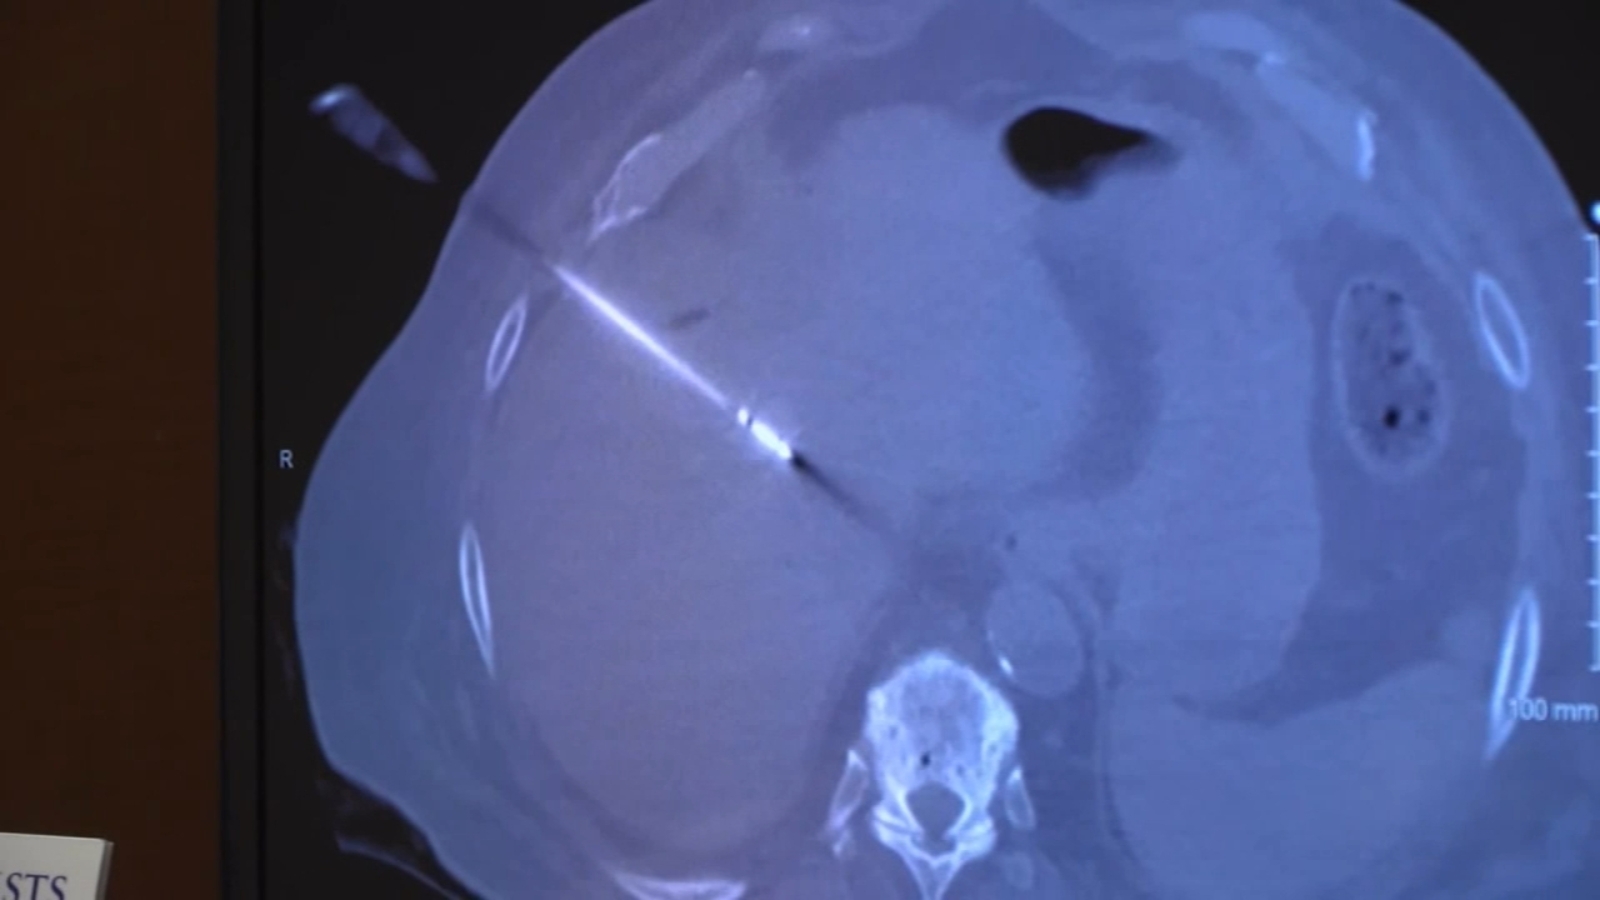

Contrastenhanced CT scan depicting renal mass or ablation site (white Kidney Ablation Below, we’ll discuss the differences. Ablation destroys tumor cells, while surgery aims to remove the tumor from the body. So it may be used for people who have only one kidney. Ablation and surgery are two treatment options for kidney cancer. Ablation involves destroying the cancer cells within the body, usually without the use of any incisions. The preferred treatment. Kidney Ablation.